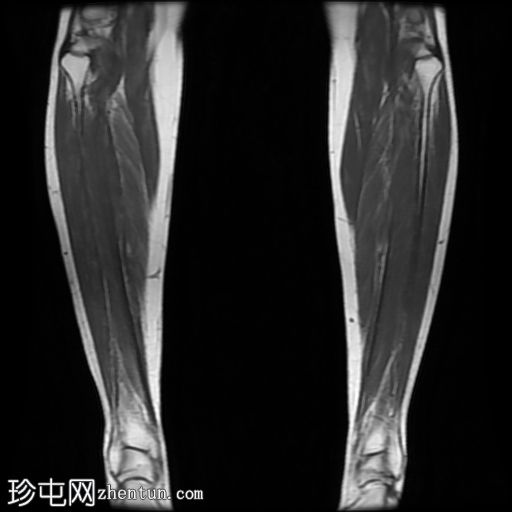

矢状位

STIR序列

轻度软组织水肿,无脓肿或积液。

腓骨正常,无骨髓水肿或皮质改变。

肌肉和肌腱正常。